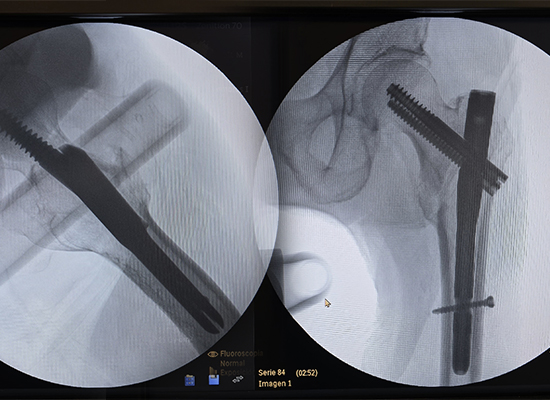

Послеоперационная рентгенограмма, показывающая фиксацию интрамедуллярным стержнем Intertan при переломе левого межвертельного отдела, Перу

Во время операции доктор Ривера отметил, что интрамедуллярный гвоздь CZMEDITECH Intertan обеспечивает превосходную биомеханическую стабильность и плавную имплантацию.

После фиксации пациенту приступили к ранней вспомогательной мобилизации. Боль значительно уменьшилась, положение конечностей было восстановлено, а последующие рентгенограммы подтвердили стабильное положение имплантата с признаками прогрессирующего заживления перелома.